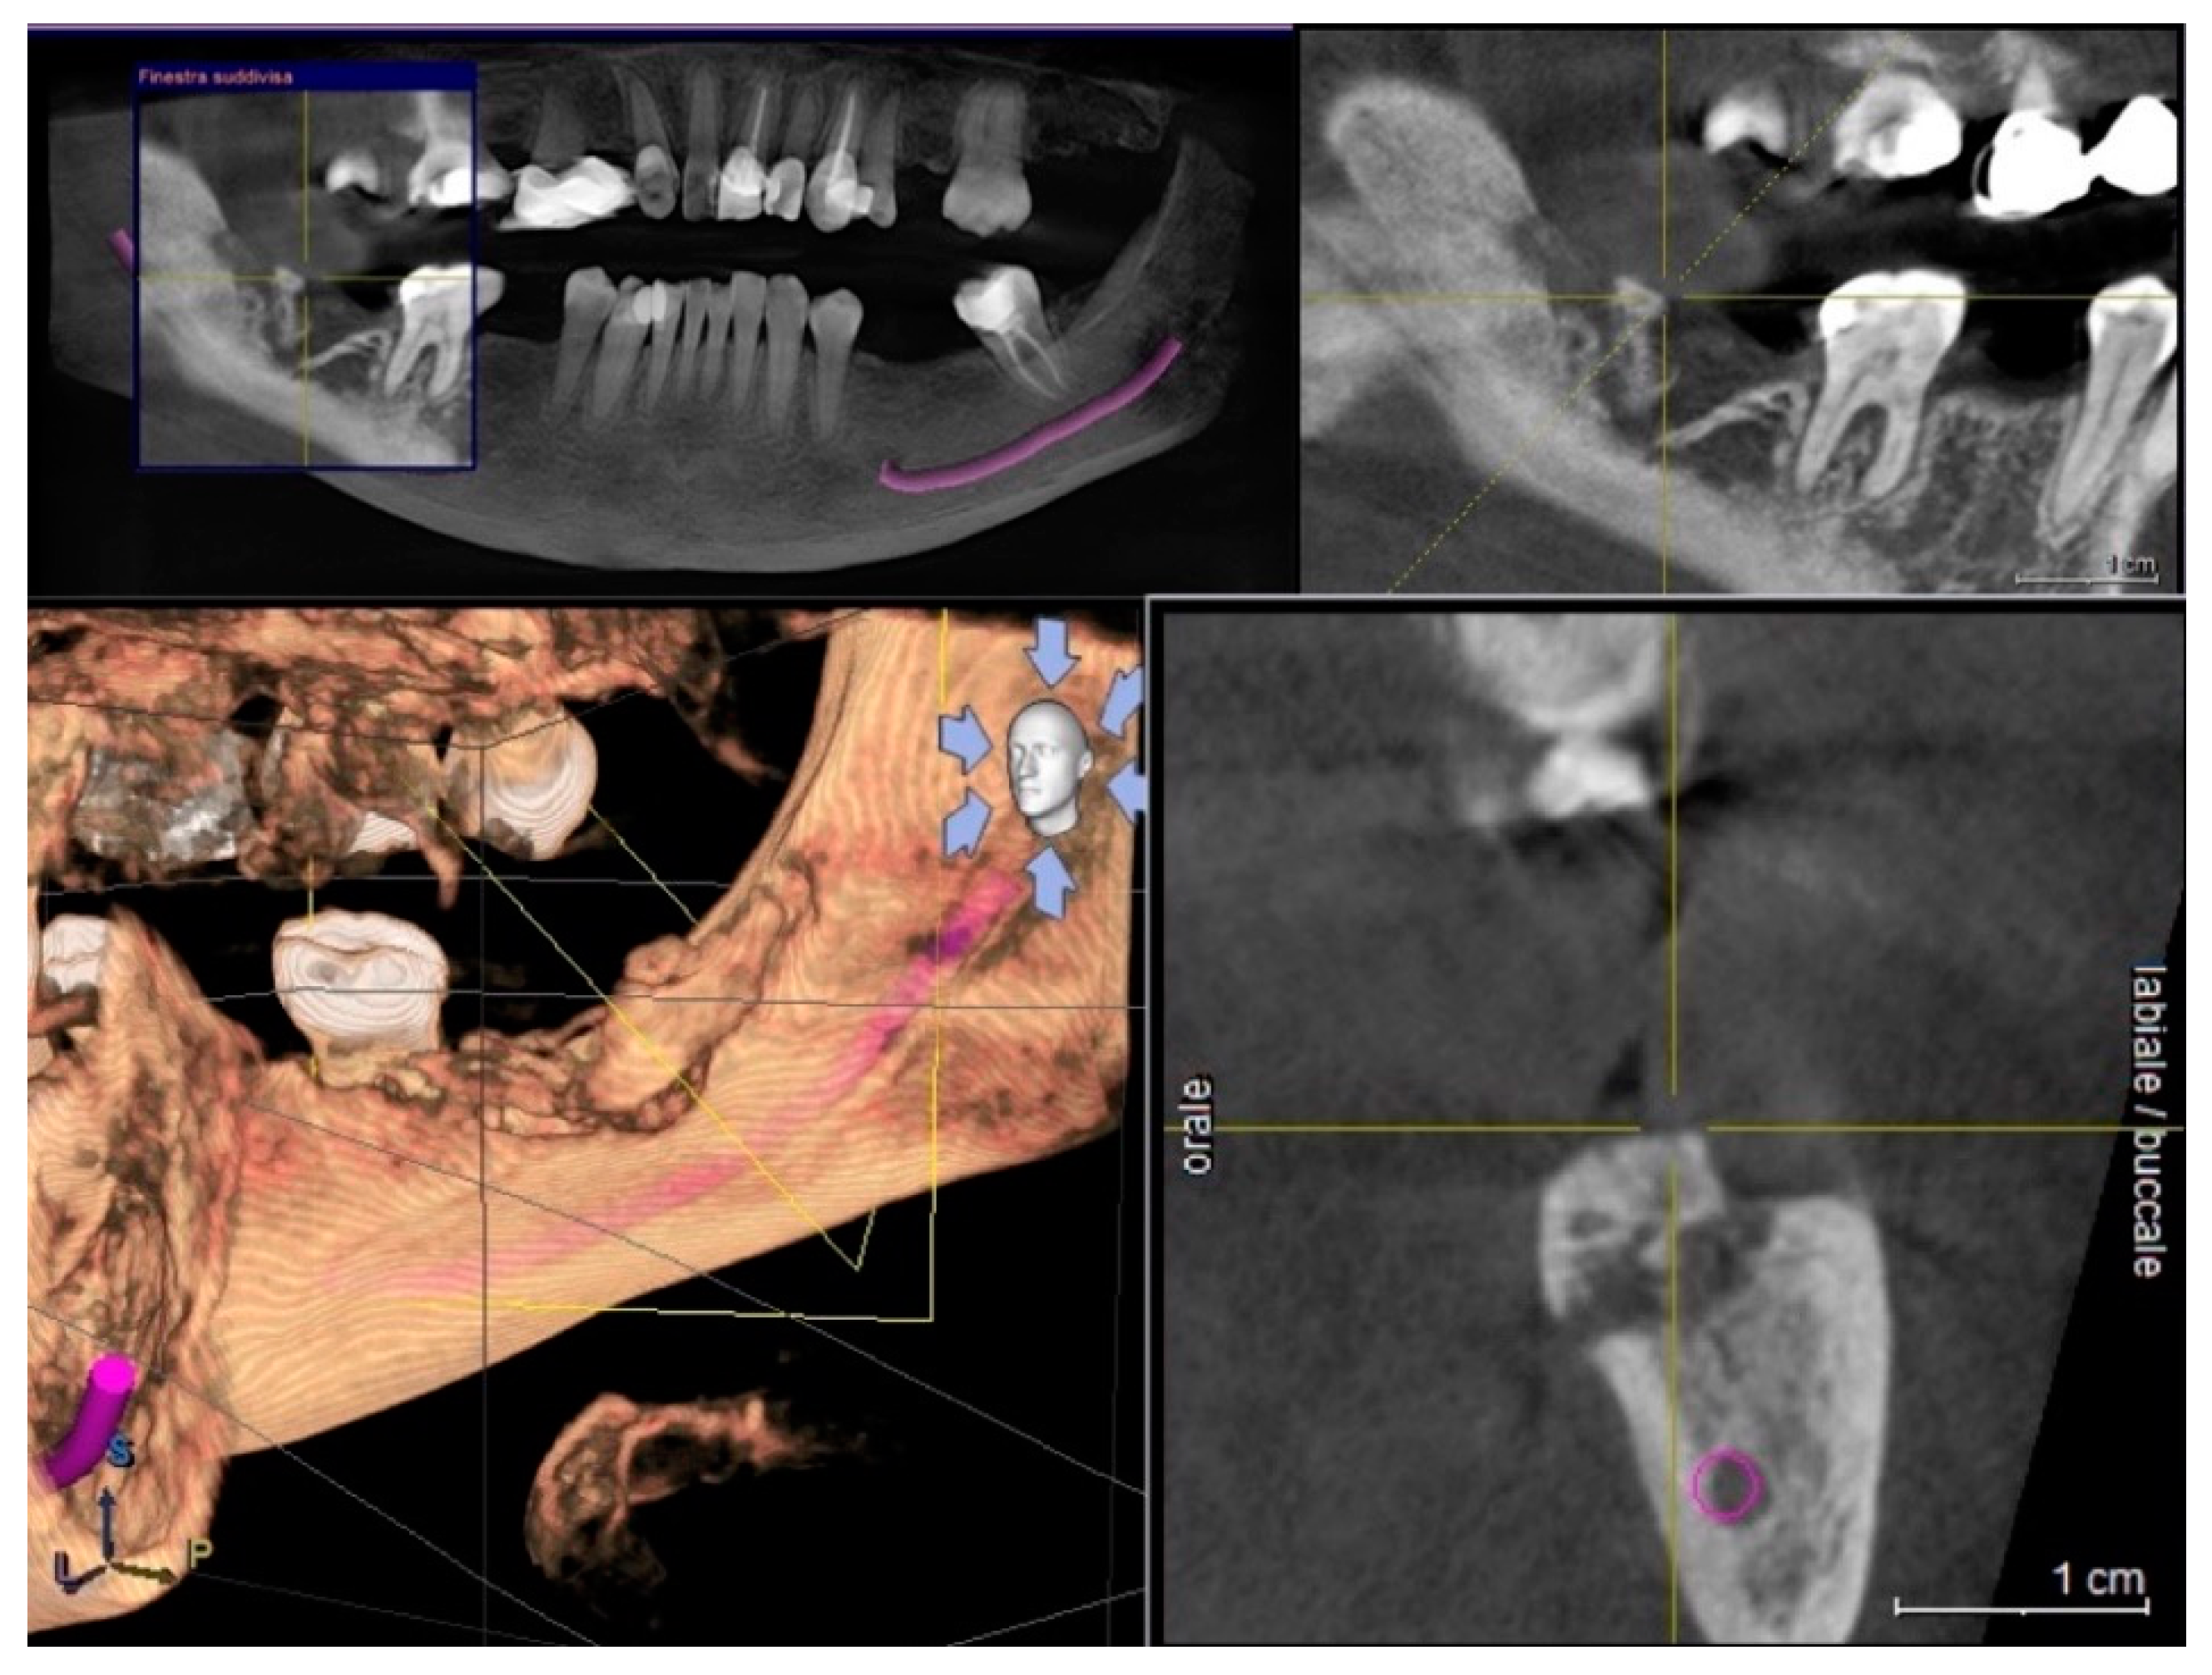

2. Materials and Methods

3. Results

4. Discussion